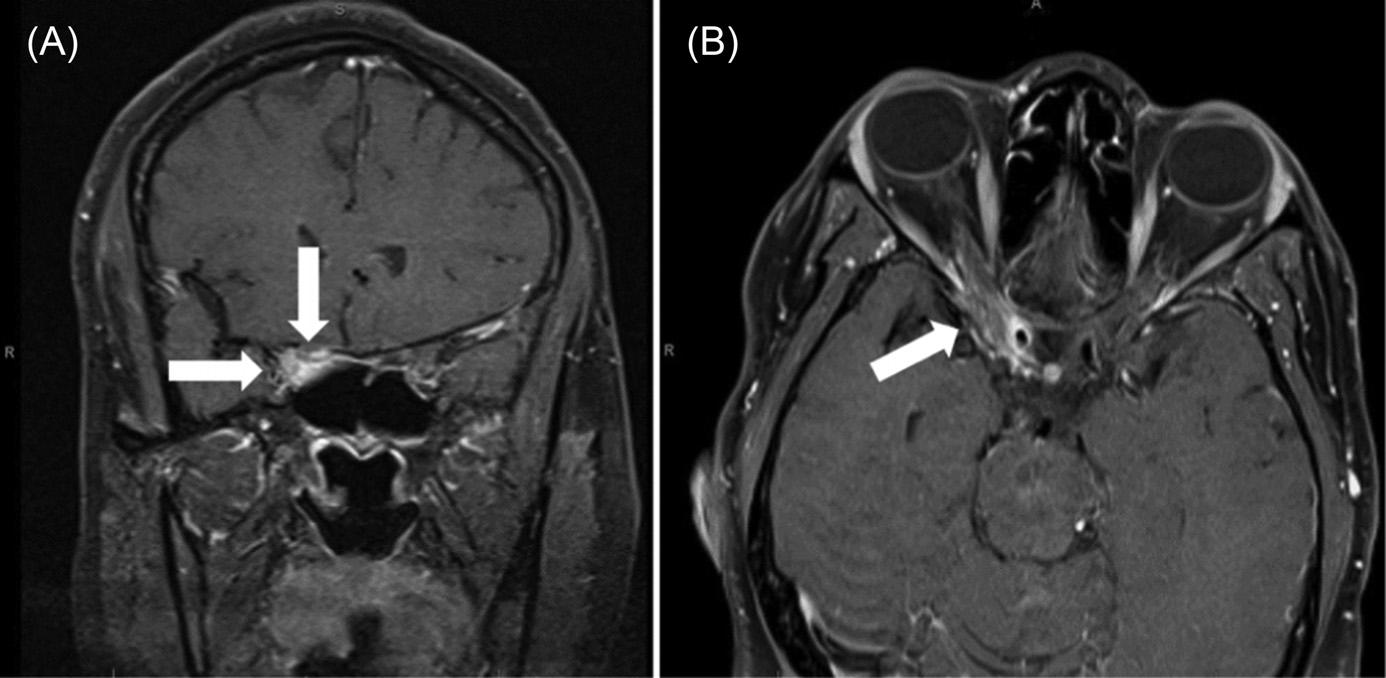

120 Face-off Droop: A Case Report of Pediatric Stroke

Duncan Robertson, Hayden F. Peirce, Marek D. Nicpon, Eric M. Otterson, Laurel O’Connor, Julia G. Rissmiller, Zachary W. Binder

176 One in a Million: A Woman Presenting with Unilateral Painful Ophthalmoplegia

Kevin Bennett, Eric Boccio